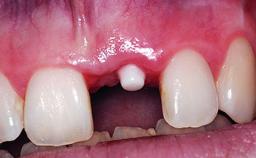

Replacement of an Ankylosed Upper Left Central Incisor: Bone Augmentation and Socket Grafting, Late Placement of an RC Bone Level Implant

A 15-year-old male patient was referred to us by his pediatric dentist in June 2004 for evaluation of treatment options for his failing tooth 21. The patient had recently seen an endodontist for internal bleaching and been advised that there had been significant resorption and ankylosis. The patient’s mother was concerned because the tooth appeared shorter than the adjacent one. His past dental history was significant for trauma (September 2001), where the tooth had been avulsed and reimplanted. Teeth 11 and 21 had been endodontically treated.